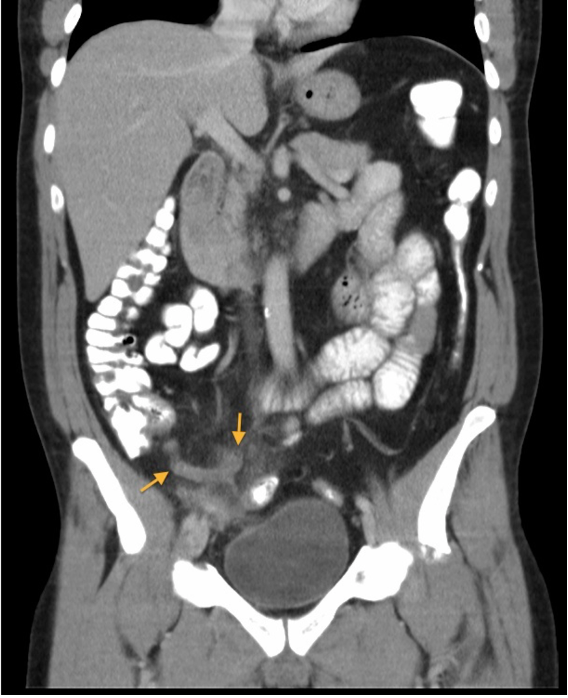

Q

Diagnose?

A

Perforeret ulcus